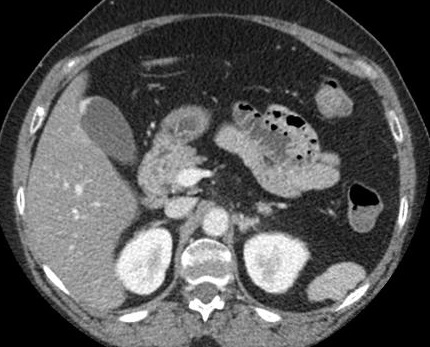

Imge TDM de polyp vesiculaire

est : image de l' aspect bourgeonaise ou polypoide a isodense

situe au fond ou au ventre de la vesicule biliaire . Sur la

technique TDM + de contrast intra veineuse la rehaussement peripherique

du polyp peut se en voyait

Image d'une polyp vesiculaire

a isodene situe au fond de la vesicule biliaire .

Image radiologique TDM + contrast en phase

arterielle et coupe axiale |

Meme cas en phase veineuse .

Image de rehaussement de contrast en peripherique du

polyp |